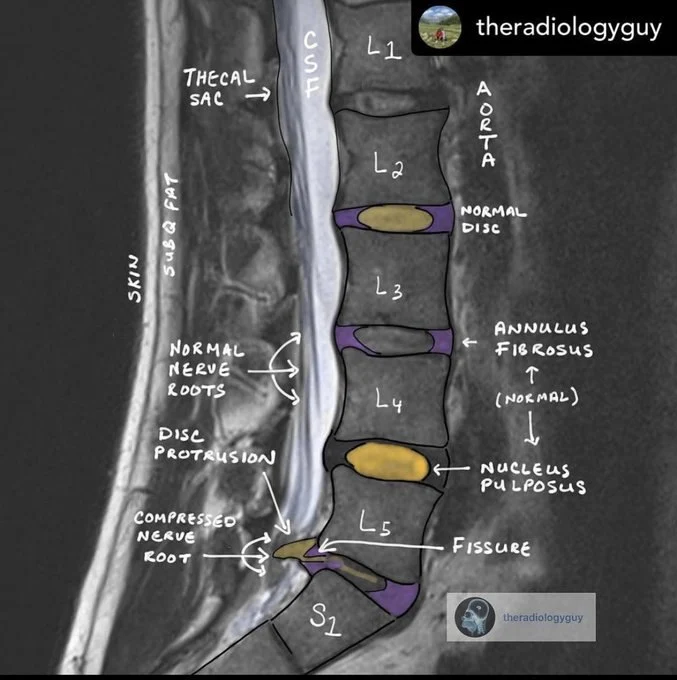

Хороший визуальный учебник по анатомии поясничного отдела МРТ и как тейпирование помогает при разрыве хрящевого кольца, защемлении диска, травмировании остеофитами.